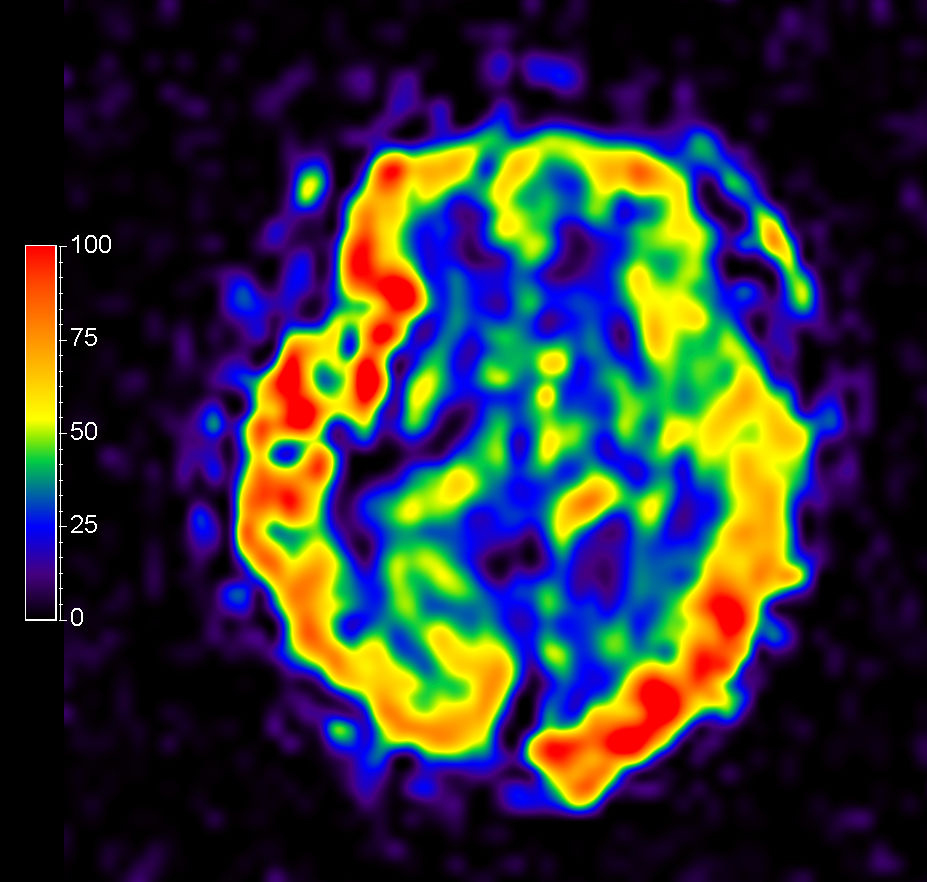

3D pCASL

-